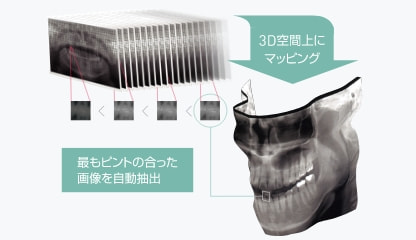

3Dオートフォーカスとは?

27mmのフォーカス域内のパノラマ画像を1mm間隔で取得。各パノラマ画像を小さいセルに分割し、その中で最もピントの合った画像だけを自動抽出して、歯列全体にピントが合った1枚のパノラマ画像を再構成します。